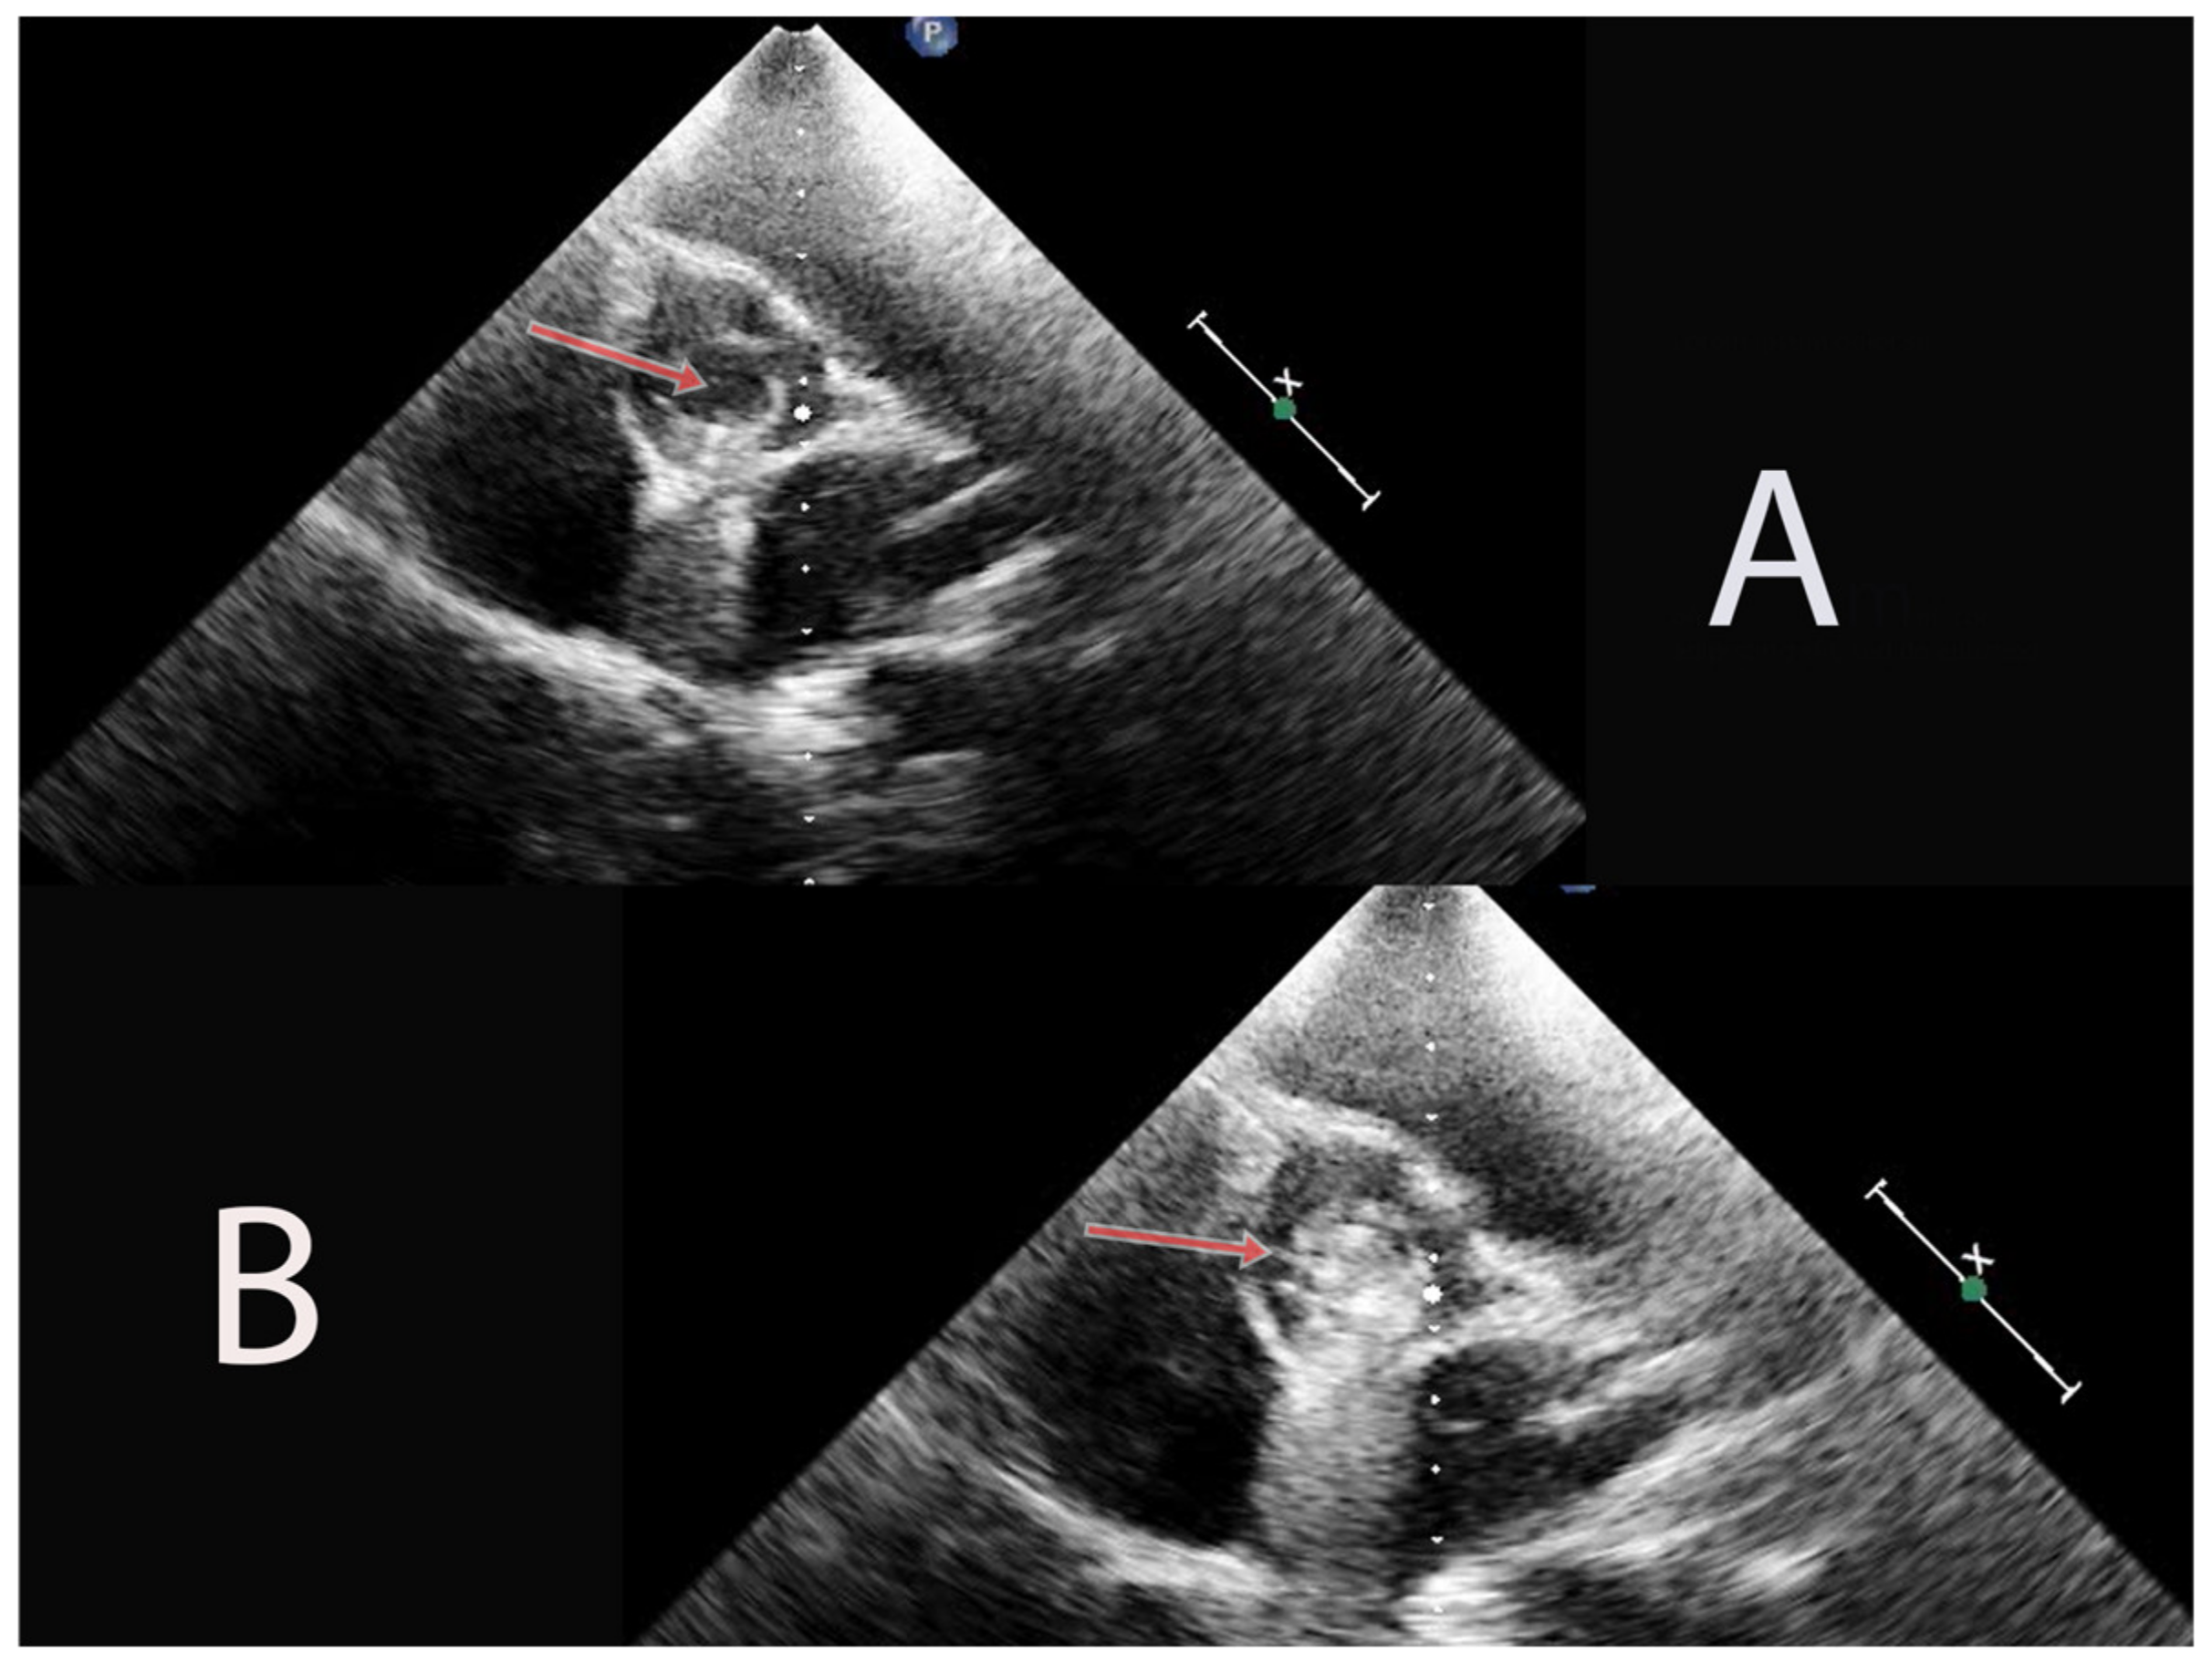

2. Case Presentation